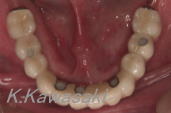

「若い頃より虫歯が多く、よく噛めない」と来院されました。

精密検査→ご相談の後、インプラントで噛みあわせの回復をする事にしました。 |

| 下あごに5本のインプラントを植立しました。今まで下の総入歯で苦労された方にとてもお勧めです。 |

インプラントでとても良く噛めるようになりました。 |

上あご→総入歯

下あご→インプラントを柱とした固定式のブリッジ。 |